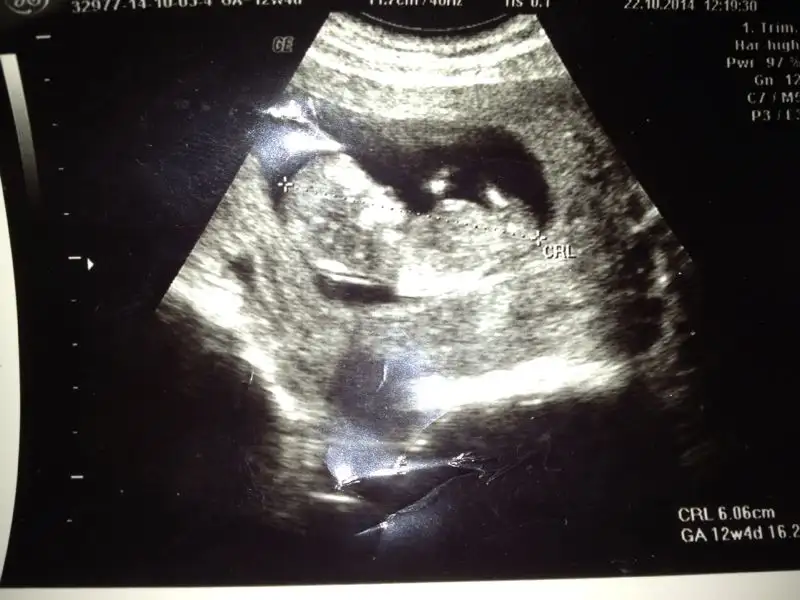

Arkadaslar aranizda nub teorisinden anlayanlar bebegimin goruntusune bakip kiz mi erkek mi yorum yapabilir misiniz lutfen?cevaplarinizi bekliyorum.

IMG-20141025-WA0000.webp

Mrb kizlar rica etsem nub teorisinden anlayanlar yardimci olabilir mi acaba? Yukledigim foto 12 hafta+2 simdiden tesekkurler..